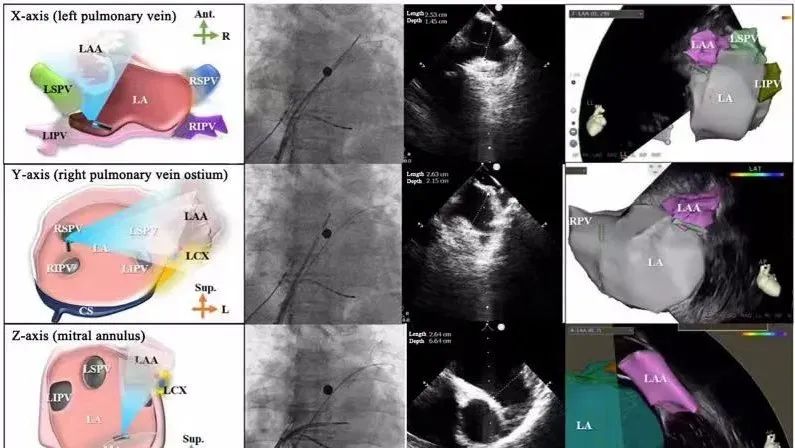

一種與心導(dǎo)管檢查相結(jié)合的超聲心動(dòng)圖診斷新興技術(shù),通過(guò)將超聲探頭置于心腔內(nèi)部,發(fā)射并接收超聲信號(hào),來(lái)精確獲取心臟解剖結(jié)構(gòu)、心臟血流動(dòng)力學(xué)等信息的實(shí)時(shí)成像。與其他影像技術(shù)相比,ICE技術(shù)具有操作簡(jiǎn)單、無(wú)輻射、安全性高、手術(shù)效率高、實(shí)用等優(yōu)勢(shì),ICE在很大程度上有望取代經(jīng)食道超聲心動(dòng)圖(TEE),成為電生理和結(jié)構(gòu)性心臟病領(lǐng)域的理想成像方式。

目前ICE技術(shù)已被應(yīng)用于左心耳封堵、房顫射頻消融、二尖瓣成形、房間隔缺損封堵等多種心臟介入手術(shù),應(yīng)用場(chǎng)景主要圍繞心臟電生理、結(jié)構(gòu)性心臟病等領(lǐng)域,目前以電生理應(yīng)用為主。數(shù)據(jù)顯示,我國(guó)結(jié)構(gòu)性心臟病介入器械市場(chǎng)規(guī)模已從2017年的4億元增長(zhǎng)至2021年的20億元,年復(fù)合增長(zhǎng)率達(dá)48.3%;預(yù)計(jì)到2025年,該市場(chǎng)規(guī)模將達(dá)到104億元,可以預(yù)見(jiàn)ICE市場(chǎng)規(guī)模也將同步高速增長(zhǎng),未來(lái)市場(chǎng)發(fā)展空間廣闊。

心腔內(nèi)超聲(ICE)技術(shù)壁壘極高,國(guó)內(nèi)主要廠商核心部件仍舊為進(jìn)口,集成了超聲和圖像處理最前端技術(shù),包括超聲探頭、線(xiàn)纜、軟件成像算法等,是當(dāng)前內(nèi)窺超聲方向最具挑戰(zhàn)的領(lǐng)域。ICE的應(yīng)用經(jīng)歷了2D平面成像、3D三維立體成像、以及4D的實(shí)時(shí)三維立體成像階段。